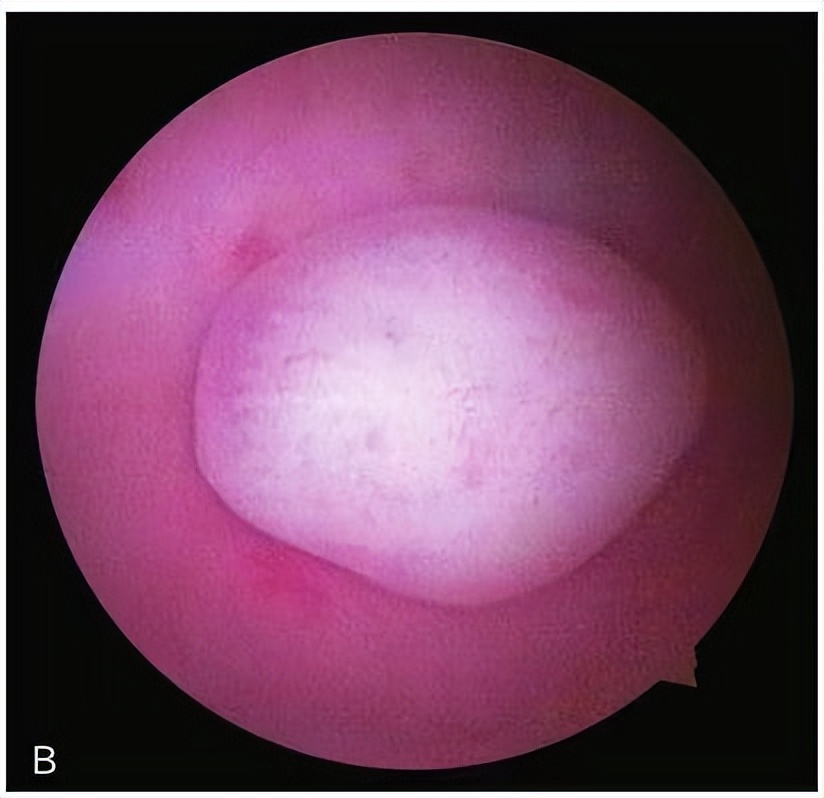

子宫黏膜下肌瘤